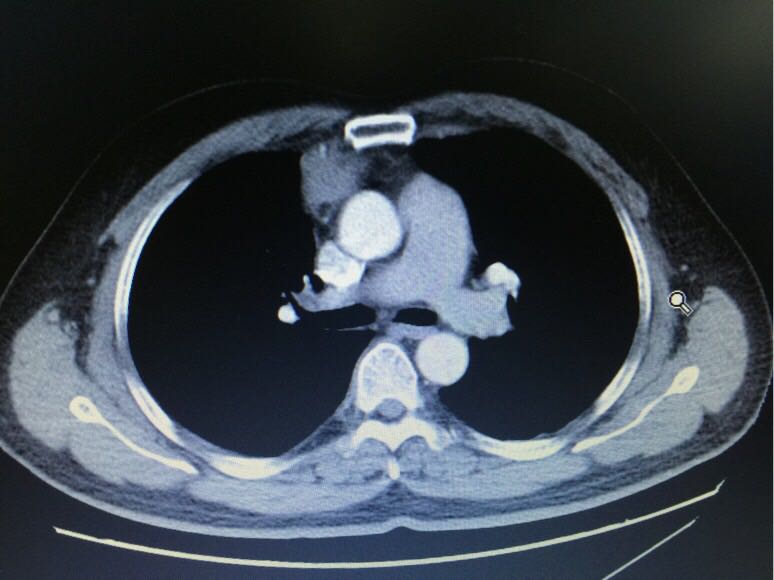

中年男性,体检发现纵膈肿物半月,无胸痛、胸闷,无四肢无力,无眼睑下垂等不适。胸部CT如下。既往乙肝病史多年,未予特殊治疗;曾行阑尾切除术。余无特殊。查体未见明显异常。本次为明确诊断住院,考虑什么?